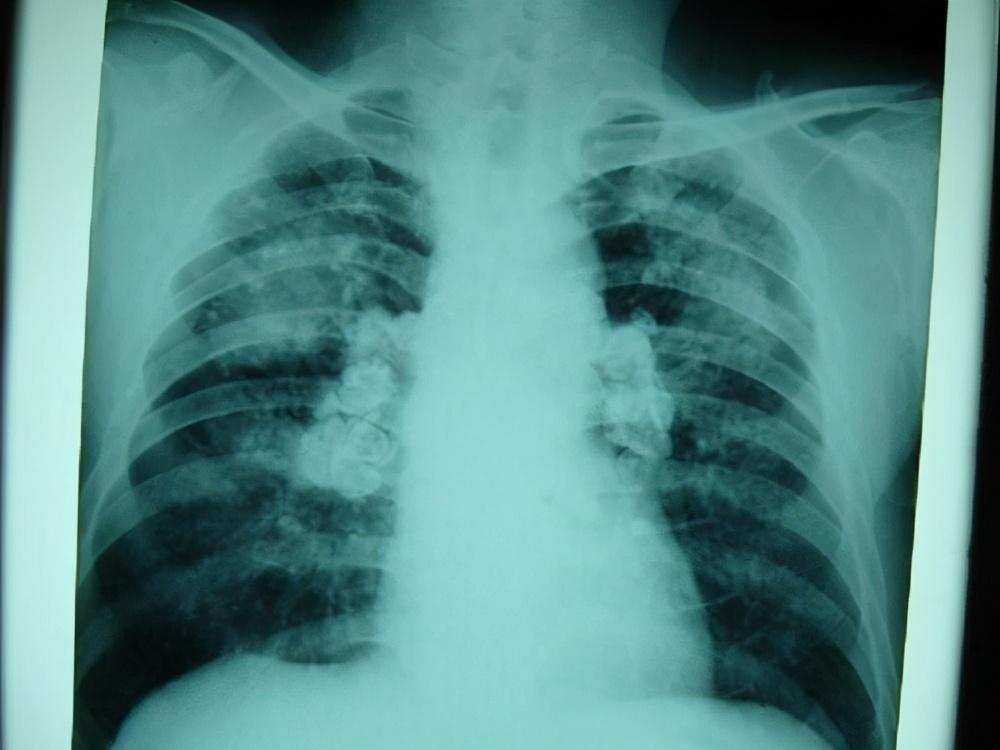

(3)X线检查

坏死型:第一种为肾盏模糊,后在肾盏处形成盲管,盲管逐渐结合,造影时呈“弓形”或“环形”图像;坏死肾乳头入盆后充填破坏,乳头呈棒状空腔,坏死的乳头充填缺损,近端扩大。坏死乳头周围可见钙,盐沉后,在扁平膜上出现环状钙化。

髓坏死型:当坏死组织在锥体深处,与肾盏不相通时,造影未发生变化,形成瘘管,肾盏连接在肾盏上。